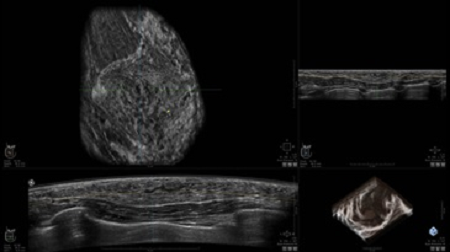

GE INVENIA ABUS – это современный УЗИ аппарат, который создан для точной и эффективной диагностики сканирования с высокой плотностью молочных желез. Выявляемость патологий раковых и предраковых стадий заболевания составляет 55%, что в конечном счете позволяет ставить врачу точные и своевременные диагнозы. Традиционные методы использования маммографии не показывают такой выявляемости, ограничиваясь лишь 3-38%.

• Получение объемных 3D изображений с возможностью покадрового просмотра

• Получение изображений в поперечной плоскости (в реальном времени) и в коронарной плоскости (статическая, для указания нахождения соска)

• Отображение объемных 3D ультразвуковых изображений, которые состоят из традиционных поперечных и воссозданных коронарных и сагиттальных проекций

• Возможность отображения полного 3D изображения

• Стандартизованная ориентация изображения: «толстый срез» в коронарной плоскости; поперечная; сагиттальная плоскость; радиальный и антирадиальный поворот изображения; просмотр исключительно области интереса

• Изменяемая толщина среза: 0,5 - 10,0 мм (шаг 0,5 мм)

• Срез: 0,5 - 2,0 мм (шаг 0,5 мм)

• 360 ° APC - отображение области по «любой точке компаса»

• Одновременный просмотр двух изображений для сопоставления в коронарной плоскости